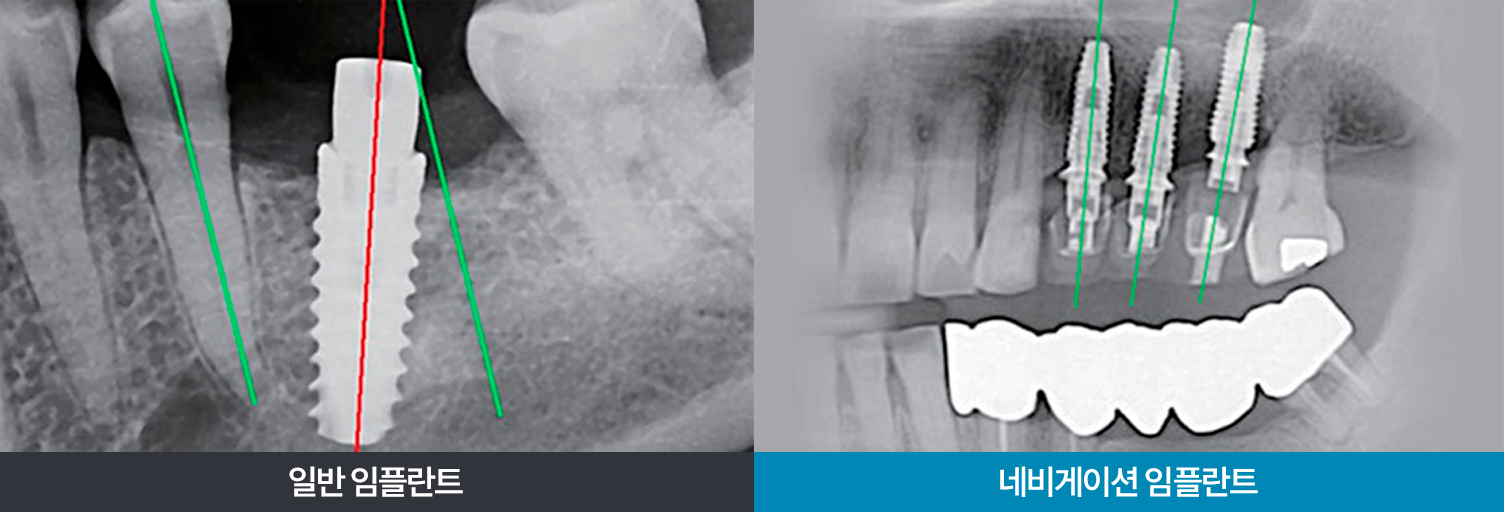

컴퓨터 분석으로 정확도 Up! 안정감 Up! 시술방법을 비교해보세요!

일반 임플란트 VS 네비게이션 임플란트

일반 임플란트

vs네비게이션 임플란트

의료진의 경험에 의존하는 계획으로

의료진의 역량에 따라 큰 차이 발생

식립계획

환자구강데이터를 바탕으로

식립 시뮬레이션 진행하여 효율적 식립 가능

잇몸을 절개하여 잇몸과 뼈 상태를

확인하면서 식립

식립방법

수술 가이드를 이용하여 식립을 진행할

최소한의 크기로 구멍을 내 식립

술자의 역량에 따라

시술 오차 가능성이 높음

정확도

모의 식립 시뮬레이션과 수술 가이드를 이용해

식립 계획에 따른 식립이 가능

잇몸을 절개하여 출혈, 통증 발생

회복을 위한 시간이 필요

회복속도절개 범위가 적어 출혈, 통증을 줄여볼 수 있고

빠른 회복 및 일상복귀 가능